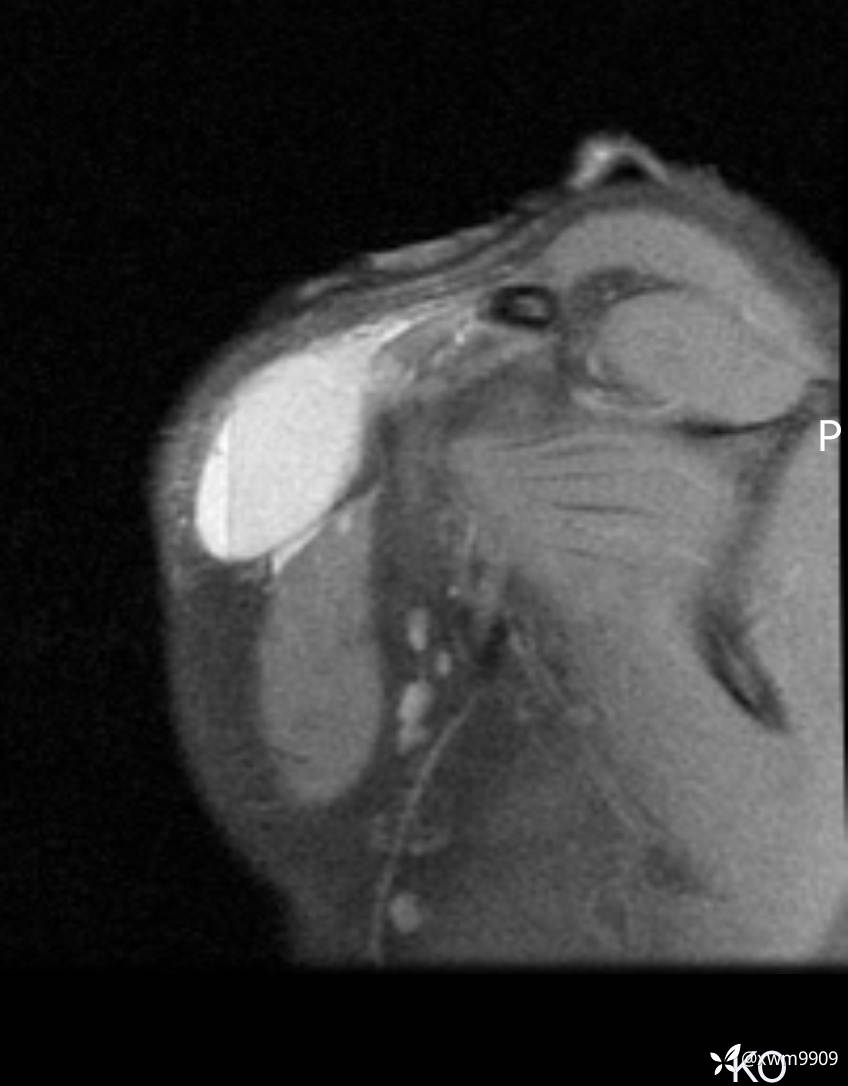

2024-03-19,门诊“摔伤右锁骨肿胀疼痛6小时。拟“锁骨骨折”要求摄:右肩关节正侧位,右锁骨轴位检查。

2024-03-20,女,6岁。因“发现右侧胸部肿物伴疼痛1天”入院。

2、现病史:家属代诉昨日洗澡时发现右胸肿物,压痛明显,查DR:未见明显异常,自行予云南白药,症状稍好转。临床拟:锁骨周围血肿收入院。

3、查体,右锁下方可及一约5x6Cm肿物,软丶边清丶未见明显发红,肤温不高,压痛明显,不可推动,稍有波动感。其他无特殊。

CT: